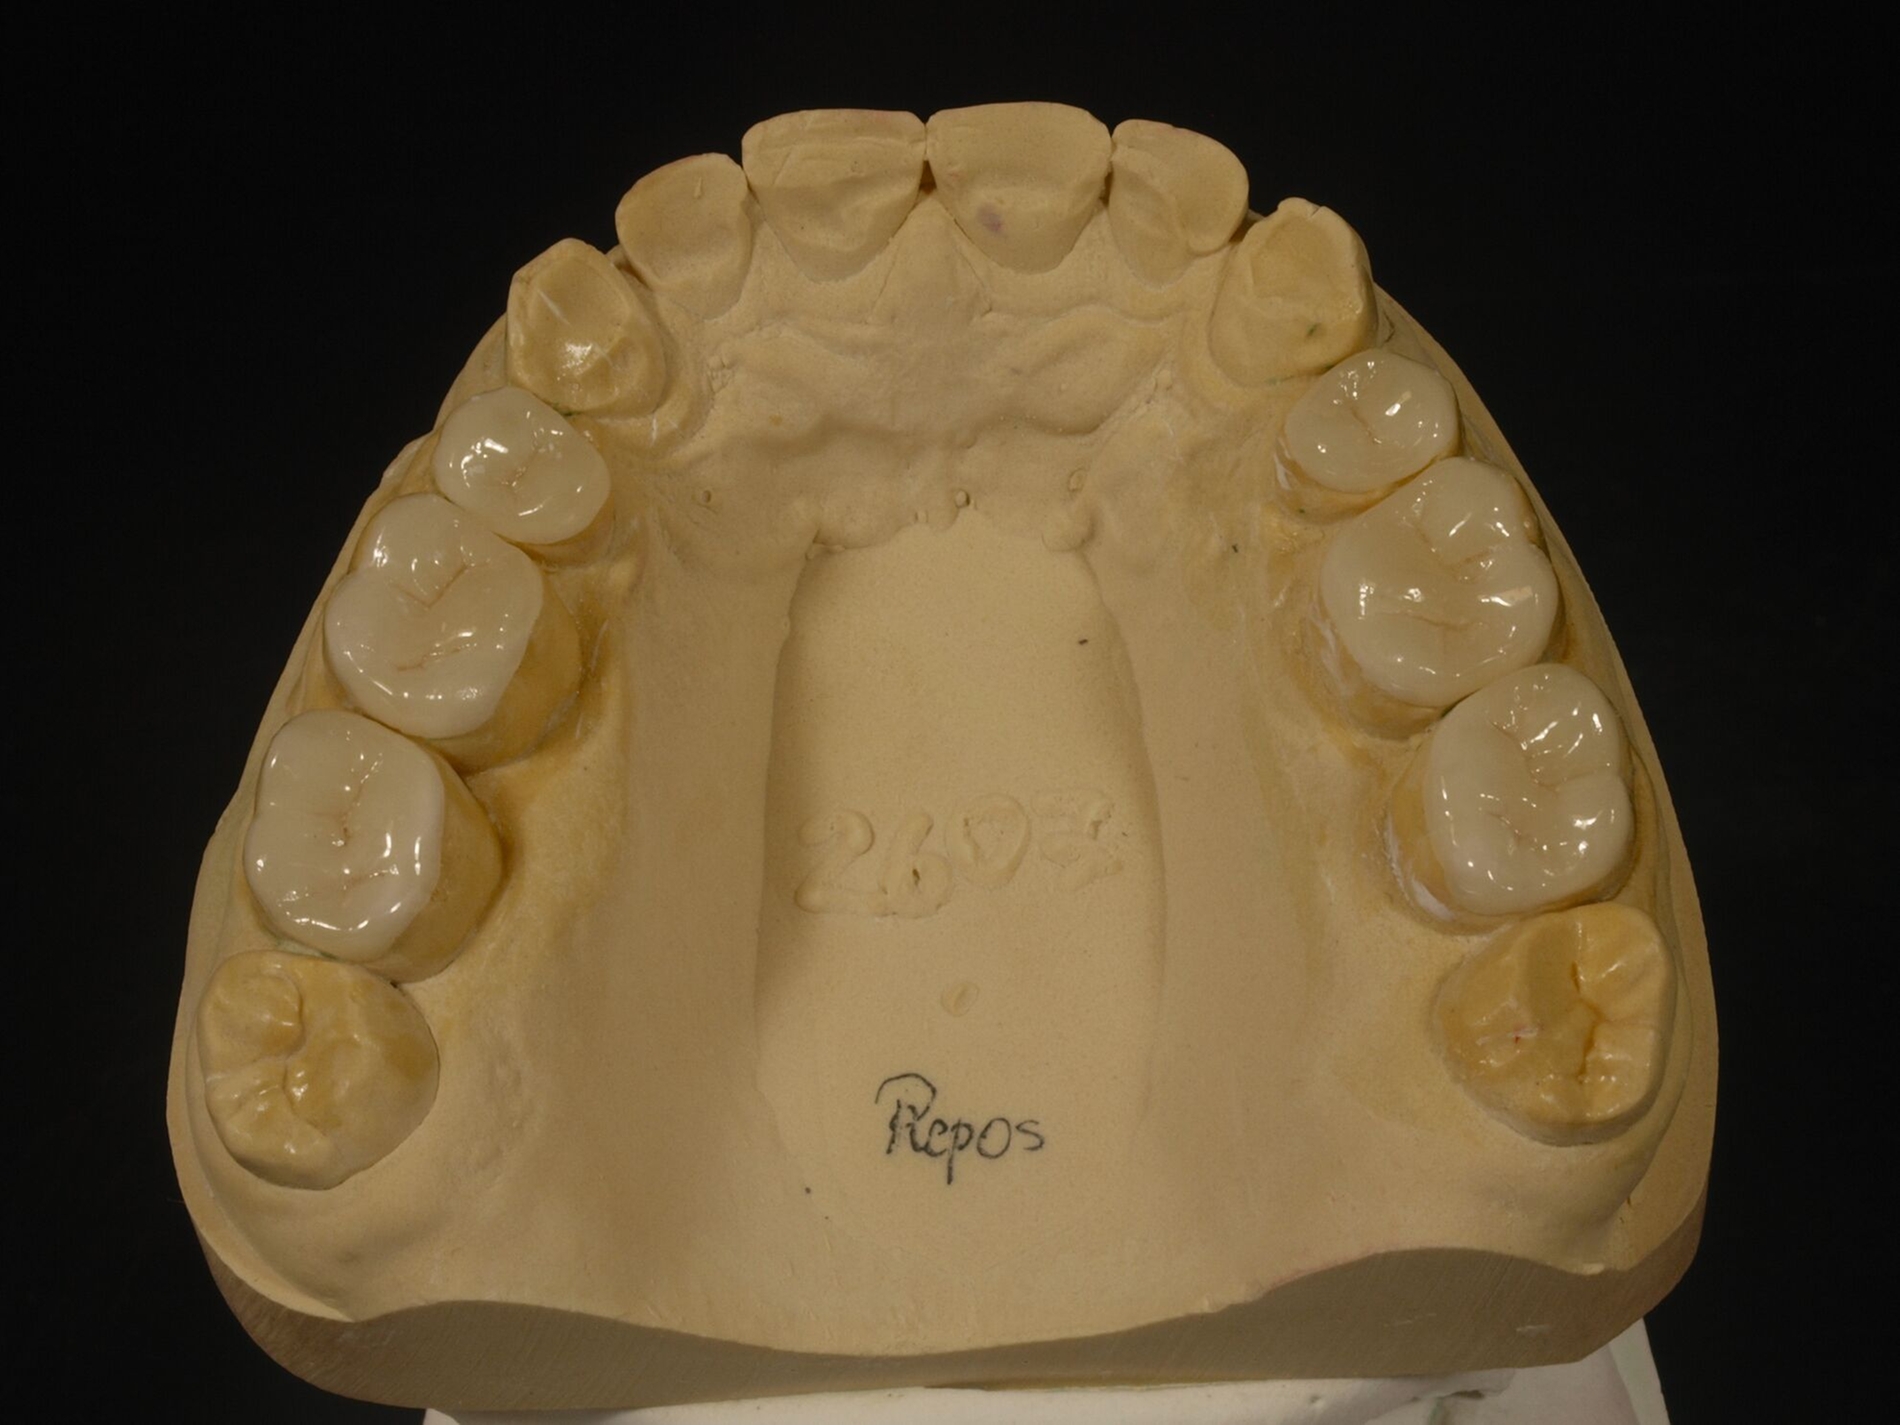

Diese Simulation der Okklusion bildet die Voraussetzung für das nachfolgende Wax-Up der geplanten Zahnform als zahntechnische Planungsgrundlage. Das so ergänzte Kiefermodell wird anschließend dubliert, als Grundlage der Herstellung neuer Kiefermodelle in neuer Kontur, auf denen wiederum speziell verstärkte Formteile für die spätere intraorale Ausformung der Komposite erstellt werden. Die Ausformung der Restaurationen aus Kompositen und ihre Aushärtung erfolgen insofern zwar intraoral „direkt“, das Gesamtvorgehen ist aber an die gleichen zahntechnischen Vorarbeiten gebunden wie eine Therapie mittels indirekter Restaurationen. Solchermaßen hergestellte Restaurationen überstehen nach Untersuchungen der engagierten Kollegen aus Zürich drei Jahre in gutem Zustand [Schmidlin et al., 2009]; nach fünf Jahren ist der Zustand allerdings beeinträchtigt [Attin et al., 2012].

Für die Behandlungsabfolge bestehen verschiedene Möglichkeiten, die unmittelbar mit der Kontrolle der Gelenkstellung verbunden sind. Generalisierter Zahnverschleiß erfordert häufig eine Behandlung aller Zähne zumindest eines Kiefers, weil der vertikale Platzbedarf zum Schutz der geschädigten Zähne eine Erhöhung der vertikalen Dimension erfordert. Dies bedingt insofern eine zeitgleiche Versorgung aller behandelten Zähne zumindest im Seitenzahnbereich, weil sonst eine ungleichmäßige Abstützung resultiert. Bewährt hat sich die Aufteilung derartig aufwendiger Behandlungen in mehrere Abschnitte. Dabei erfolgt im ersten Abschnitt die Abstützung im Seitenzahnbereich in neuer VD, in der Regel einhergehend mit einer semipermanenten Versorgung der Frontzähne zur Wiederherstellung der dynamischen Führung in neuer VD. Im begründeten Ausnahmefall kann dieser Schritt entfallen, etwa bei unmittelbar nachfolgend geplanter Behandlung der Frontzähne; in dem Fall erfolgt die Steuerung der dynamischen Okklusion in der Zwischenzeit mit einer entsprechend gestalteten Okklusionsschiene, die auch tagsüber getragen wird (Abbildung 11).

Nach der Eingliederung der Restaurationen hat sich eine umgehende Abformung bewährt, die ebenso umgehend in Modelle überführt wird, um zu prüfen, ob die Restaurationen gleichmäßig aufeinandertreffen. Beim Folgetermin zum Finetuning liegen diese dann vor und erlauben im Zweifelsfall eine umgehende okklusale Korrektur. Wichtig ist, den sensorischen Eingewöhnungsstress der Patienten abzufangen. Das gelingt am Tag der Eingliederung durch eine hydrostatische Sofortschiene (The Aqualizer, Bausch Dental, Köln; AquaSplint mini, TeleDenta, Chemnitz; FreeBite Gel, MediPlus, Unterleinleiter). Spätestens nach dem Finetuning erfolgt eine neue Abformung als Grundlage für die Herstellung einer neuen Okklusionsschiene. Die AWMF-Leitlinie zu vollkeramischen Kronen und Brücken verlangt, dass diese bei Bruxismus zum Schutz der Restaurationen dauerhaft getragen wird. Diese Okklusionsschiene kann im Ober- oder Unterkiefer getragen werden, die eingestellte Kieferposition entspricht der durch die Restauration eingestellten Position.